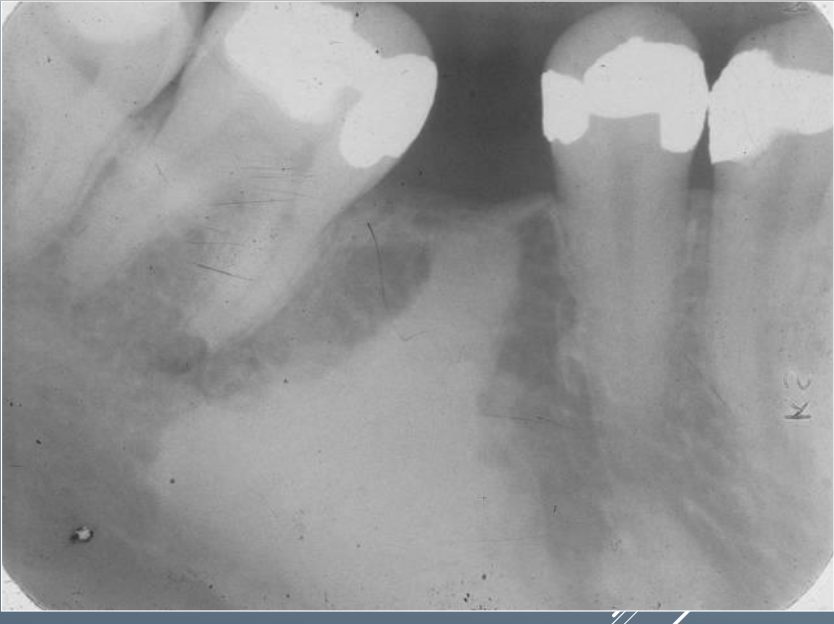

17

Q

Does teeth surrounding CONDENSING OSTEITIS vital or non vital

18

Is condensing osteitis associated with pathosis?

19

What’s this?

A

CONDENSING OSTEITIS

CHRONIC FOCAL SCLEROSING OSTEOMYELITIS